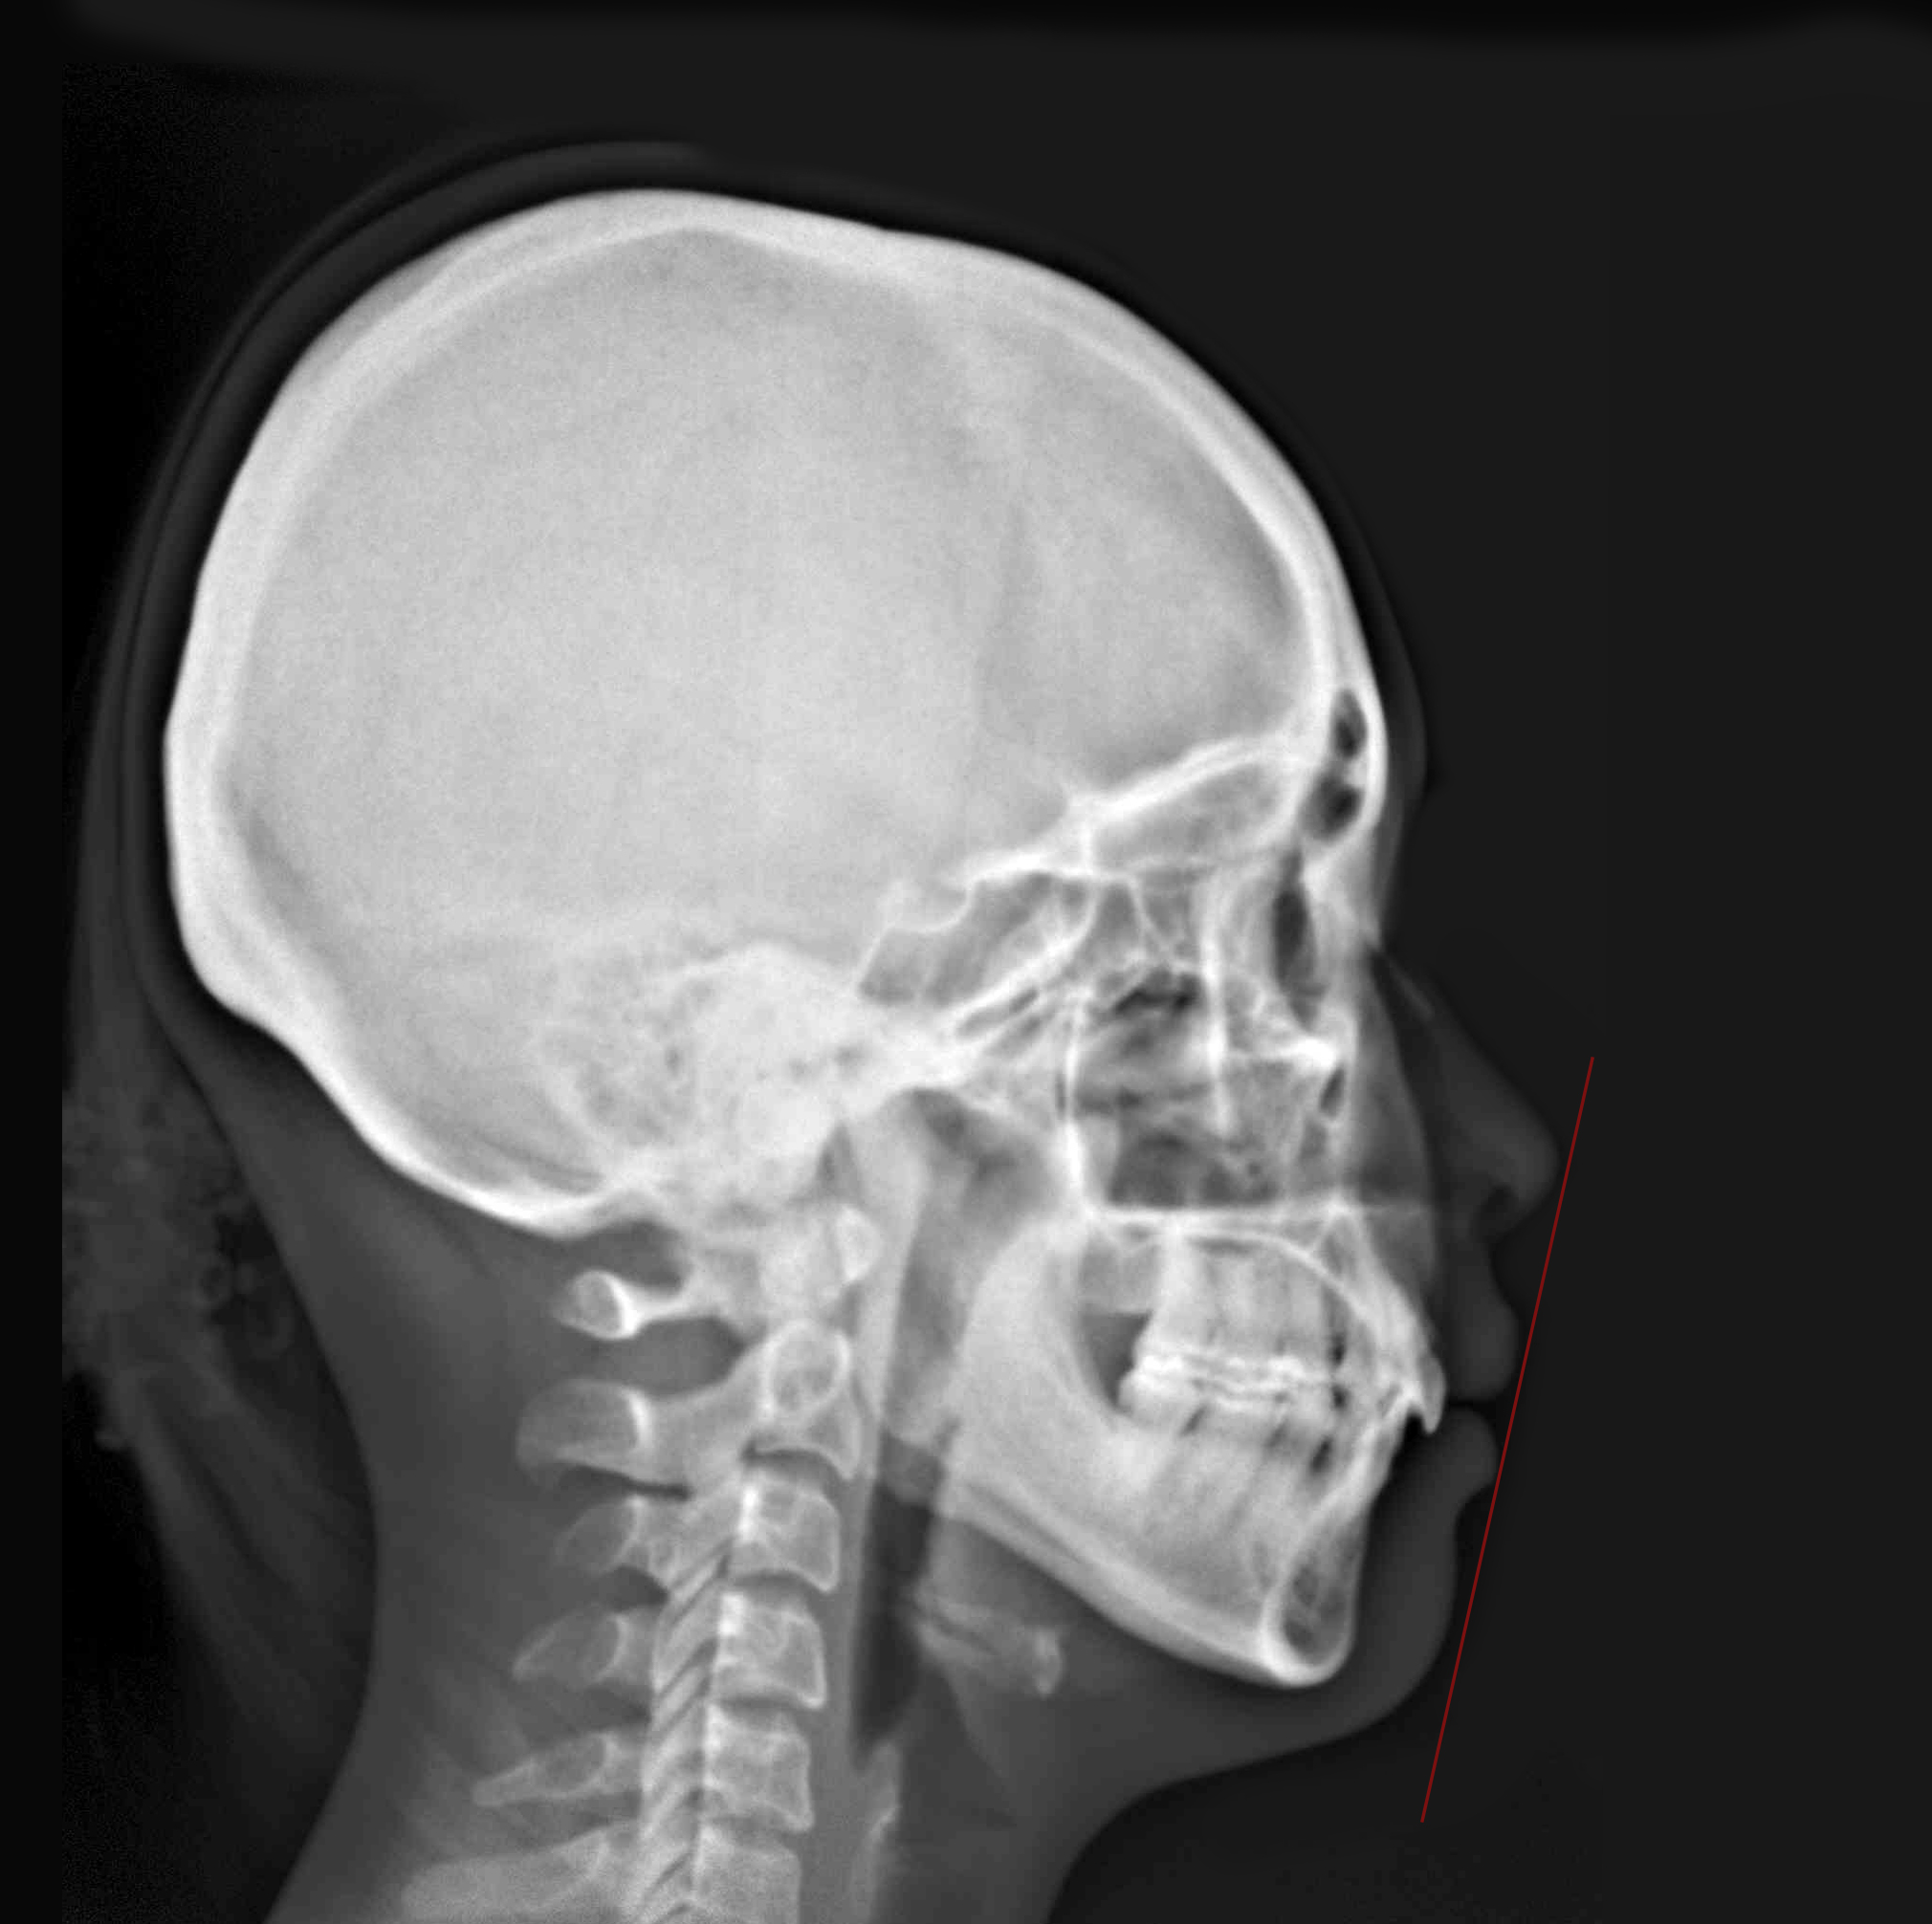

隱適美拔牙改臉型 (一) 首頁 案例分享 齒顎矯正 隱適美拔牙改臉型 (一) 拔牙改臉型 當初客戶最想改善的暴牙...... 經過拔牙四顆小臼齒,與醫師完美的合作,最終也改善了臉型與暴牙,笑起來也更有自信~ 聲明:本所療程皆由專業醫生評估後,依照個人口腔狀況進行治療。因每位患者個別狀況不同,術後狀況也不盡相同,需親來本所由醫生評估。